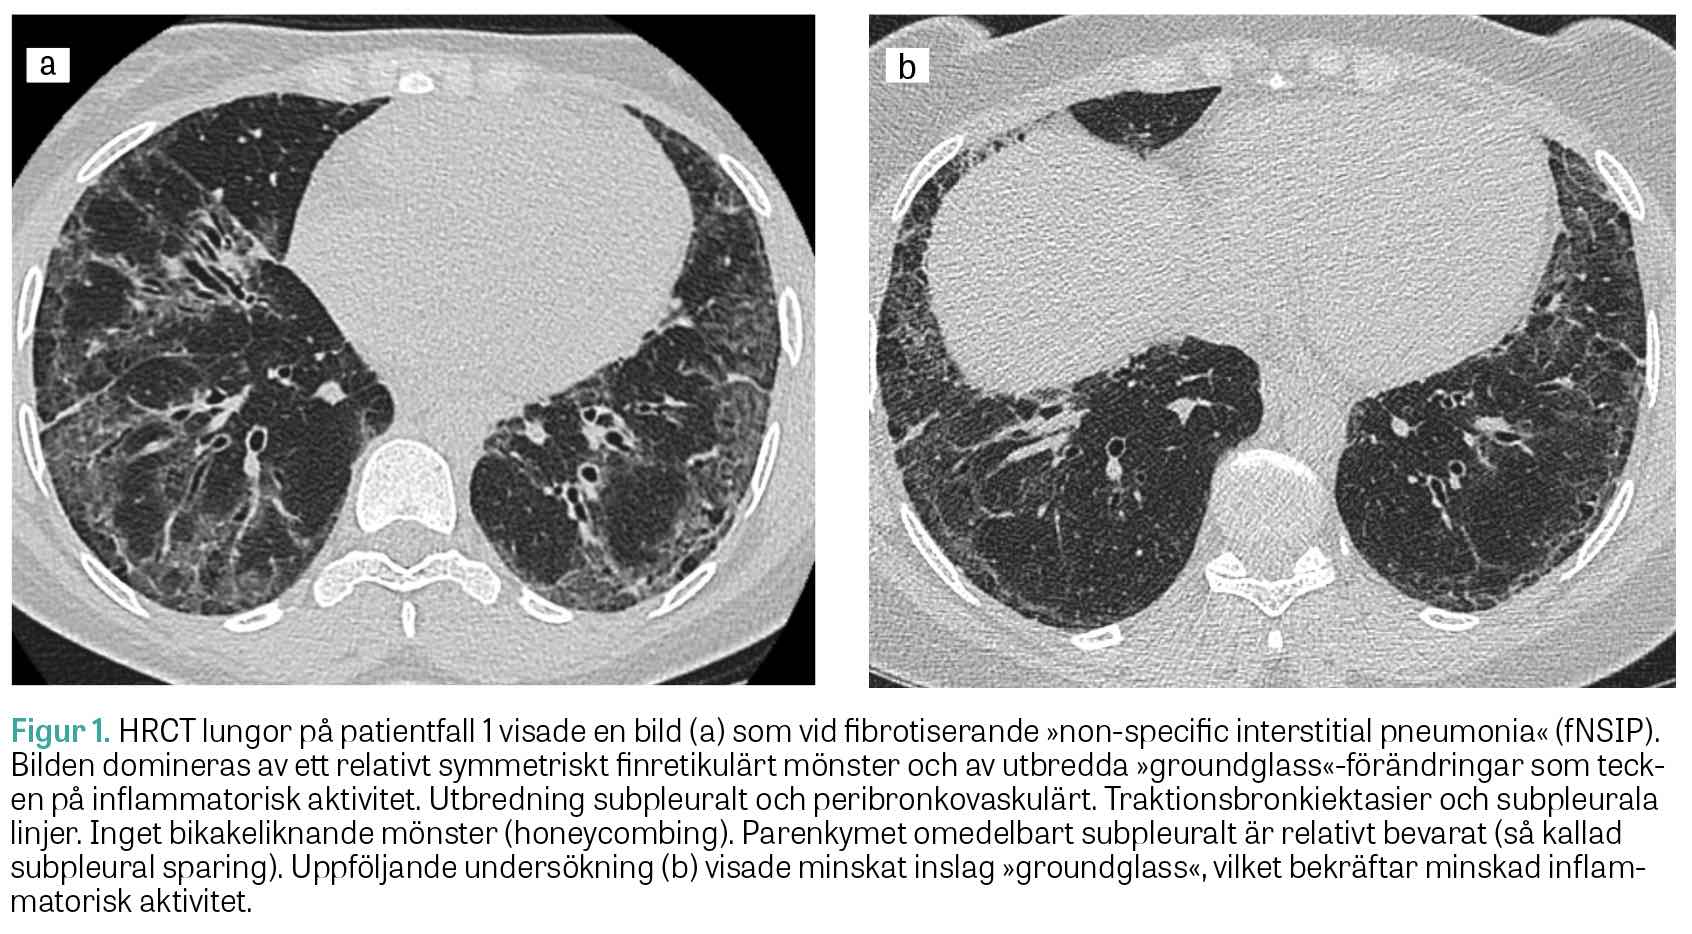

Fall 2. Den andra patienten är en icke-rökande tidigare frisk 65-årig kvinna, som insjuknade med hosta och andfåddhet och remitterades från vårdcentralen till lungmedicinsk klinik för utredning. HRCT lungor visade bild av NSIP. Bronkoskopi och bronkoalveolärt lavage utfördes utan att man såg tecken på infektion. Autoimmun serologi visade negativa ANA och positiva anti-Ro52-antikroppar. Spirometri visade TLC 65 procent, DLCO 45 procent och FVC 67 procent av förväntad funktion. Hon fick påbörja behandling med prednisolon (30 mg/dag), utan nämnvärd klinisk förbättring. Ny HRCT lungor visade påtaglig progress av fibros och även »ground glass«-förändringar förenliga med pågående inflammatorisk aktivitet. Spirometri visade oförändrade värden. Vid diskussion på en multidisciplinär konferens föreslogs komplettering med myositantikroppar, som visade stark positivitet för anti-PL-12 och anti-Ro52. Diagnosen anti-PL-12-positivt antisyntetassyndrom med isolerat lungengagemang kunde fastställas 12 månader efter symtomdebut.

Behandling inleddes med metylprednisolon (500 mg) intravenöst i 3 dagar, följt av prednisolon (50 mg × 1) samt cyklofosfamid (500 mg) intravenöst varannan vecka som på grund av levertoxicitet fick bytas mot infusioner med rituximab (1 000 mg) intravenöst med 2 veckors mellanrum. Underhållsbehandling gavs sedan med mykofenolatmofetil och prednisolon. Efter insatt behandling upplevde patienten minskad andfåddhet och hosta. Uppföljande HRCT lungor var utan inflammatorisk aktivitet eller tecken på progress av fibros. Spirometri två år senare visade förbättrade värden med TLC 74 procent, DLCO 64 procent och FVC 89 procent av förväntad funktion. Prednisolonbehandlingen utsattes då sjukdomsaktiviteten bedömdes som låg.

Figur 2.